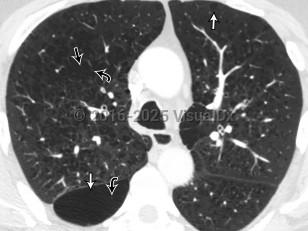

Chronic obstructive pulmonary disease (COPD) is a preventable and treatable condition with both pulmonary and extrapulmonary effects. Despite this, it is the third leading cause of death worldwide. COPD is characterized by chronic airflow obstruction that is not fully reversible. The disease is usually progressive and due to an abnormal inflammatory response in the lungs. Extrapulmonary manifestations include systemic inflammation, weight loss / nutritional deficiency, anemia, skeletal muscle dysfunction, and an increased risk for cardiovascular comorbidities.